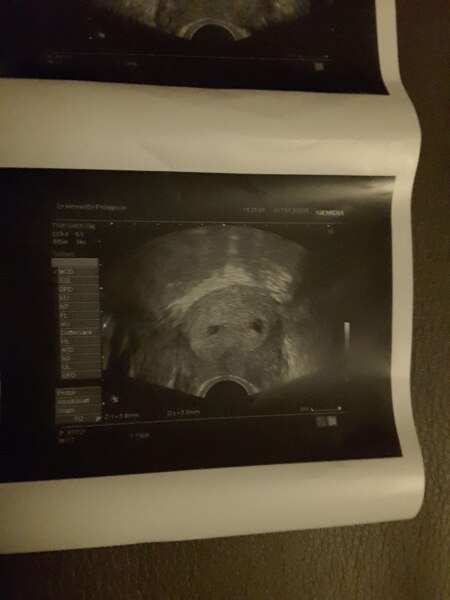

Hallo ihr lieben ich war am Freitag beim Arzt der zwei fruchthöhlen entdeckt hat. Er sprach davon das es Zwillinge sein können mal sehen win es beim nächsten Arzt Besuch aussieht. Bin da in der 5 ssw gewesen. Letzte Periode war am 4.11.15 mit 32 Tage Zyklus. Den nächsten Termin habe am 24.12. , das ist noch sooooooo lang hin . Was meint ihr vom Bild her? Beide sind fast gleich groß. Wenn zwei fruchthöhlen da sind heißt es immer beide sind befruchtet? Würdet ihr bis zum 24.12 warten oder doch schon eher hin?

Bild zu Zwillinge !? wann würdet ihr noch mal zum Arzt? - Forum für August - Mamis